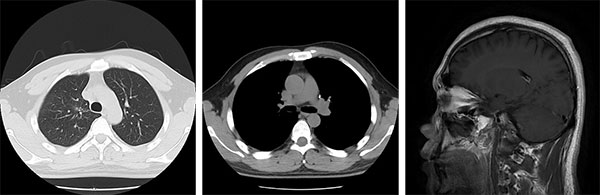

2016年5月,31岁的小申连续多日出现咳嗽、痰中带血症状,左侧后背还时常隐痛。起初他以为是熬夜工作劳累所致,直到症状持续加重,才在家人催促下前往当地医院就诊。胸部CT显示左肺上叶存在占位性病变,进一步检查后发现,癌灶已转移至右肺及纵隔淋巴结,头部MRI更提示脑部存在多发转移灶;支气管镜活检最终确诊为肺腺癌。“拿到病理报告,被医生告知所患疾病是晚期肺癌(Ⅳ期)伴脑转移的那天,我在医院走廊里坐了很久,反复问自己:为什么是我?”无烟酒习惯、无家族肿瘤病史的小申在医院走廊枯坐良久,始终无法接受自己已是晚期癌症的事实。

“刚开始服药时,心里总有些忐忑,怕效果不如预期。”服药第3天,咳嗽症状明显减轻;8周后复查,胸部CT显示肺部病灶显著缩小,阻塞支气管的肿瘤组织基本消失;70天,头颅核磁也提示脑转移灶体积缩小、部分微小病灶完全消失。小申的抗癌小本本上记录着他每一天的状况改善。就这样,在治疗的第三个月,小申就重新回到了工作岗位,气色越来越好,变得和常人无异。

治疗前(2016年12月)